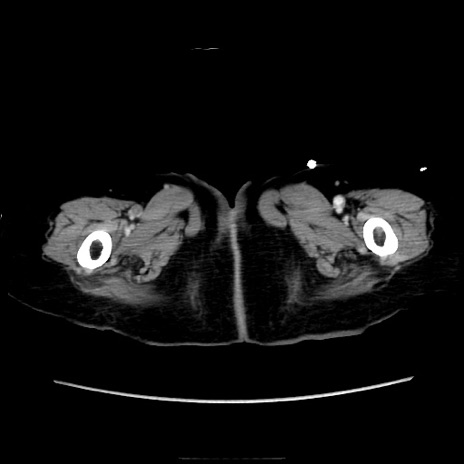

症例40(横断像)

横断像